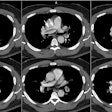

There is evidence of arterial wall thickening (greater than 1.5 mm), stenosis, annuloaortic ecatsi,a or aneurysm formation [1,2,3]. Lesions are long, segmented, and tapered at both ends [2].

PET imaging will demonstrate abnormal tracer uptake in the aortic arch or large thoracic arteries in more than half of affected patients [3].